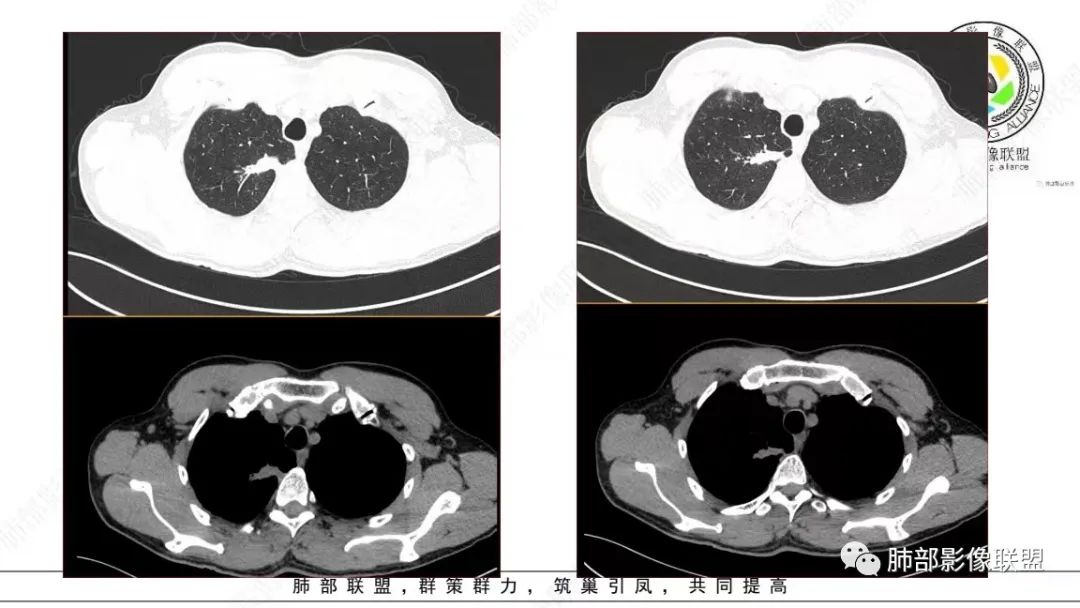

还是和病变成分有关。在肿瘤当中,或者上皮间质转换比较明显等,可以有不同的强化方式。当然也可以表现为延迟强化,可以动脉期明显强化。和肿瘤的具体类型,以及具体病变的病理成分有关。多层面观察,病变是明确有细支气管进入的,而且明确的有铸型的低密度粘液栓。

总结一下:肺内,周围型病变,含有黏液/纤维的,有收缩力的,支气管进入,有粘液栓形成的病变。常见疾病谱当然就是腺癌、特别是结节型的黏液腺癌,还有一些非特异性的慢性炎、结核等。容易形成支气管粘液栓的病变很多,慢性病变中,除了非特异性感染,一些细菌,比较常见的就是结核、曲霉。但是,支气管进入,有粘液栓形成的,周围型,肿瘤性病变,却少之又少。疾病谱中,最常见的就是气管腔内占位,以远粘液栓是继发改变。比如鳞癌、类癌。

在细支气管腺瘤的文献中,病例较少,没有看到过提到有粘液栓形成的病例描述。细支气管腺瘤的病理要点中,1,可以见到细支气管进入病灶。2.双层细胞。细支气管水平的病变,当然就可以有纤毛,有可以分泌黏液的细胞。在细支气管腺瘤中,形成的粘液,可以弥散在组织间隙,也可以聚集,形成粘液湖。更容易经过细支气管排出,形成空洞。类似于腺癌的空泡。这个病例虽然有延迟强化,收缩力比较强,也有支气管粘液栓,但是比较难解释这么低密度的,有延迟强化的,可疑粘液成分。

这个病例还可以深挖,图像有点少,我感觉部分层面可疑少许磨玻璃。最难鉴别的是结节型黏液腺癌,特别是细支气管腺瘤的收缩力比较弱的时候。这个病例收缩力太强,结节型黏液腺癌不太好解释。结合病理及影像表现,这个病例最终诊断:倾向于细支气管腺瘤、合并一些非特异性的感染、支气管内粘液栓形成。细支气管腺瘤,疑难。实性的细支气管腺瘤,更疑难。再合并感染,难上加难。不讲理的一个病例。